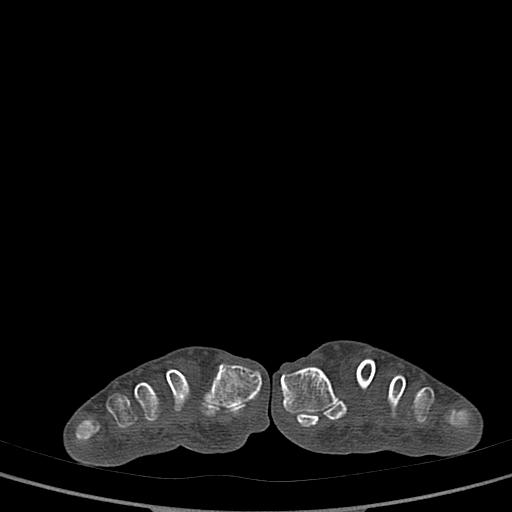

标题: CT13415:M72Y,跖趾关节病变,请会诊 [打印本页]

标题: CT13415:M72Y,跖趾关节病变,请会诊

男72岁左侧跖趾关节肿痛15年,查压痛。